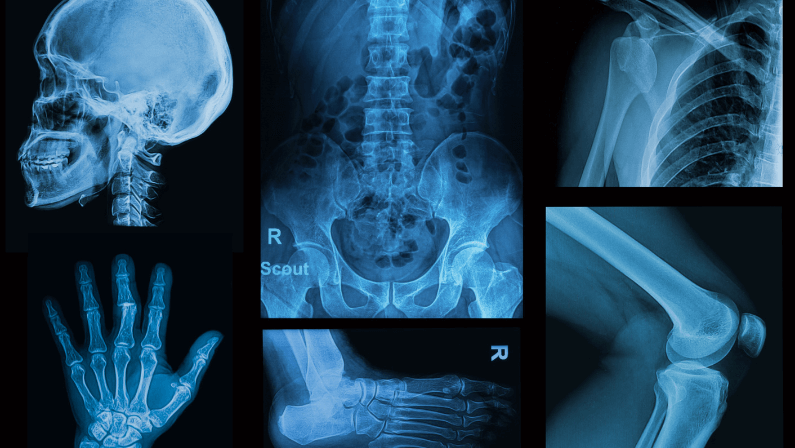

They are primarily used for imaging the internal structures of the body, such as bones, organs, and tissues. X-rays play a crucial role in detecting fractures, infections, tumors, and other abnormalities within the body.

Denser tissues, such as bones, absorb more X-rays and appear white on the resulting image, while less dense tissues like muscles and organs appear in shades of gray.

X-ray images can be captured on film or digitally, allowing doctors to analyze and diagnose various conditions.

- Chest X-rays: These are used to detect lung infections, tumors, heart conditions, and other chest-related issues.

- Bone X-rays: These exams are used to diagnose fractures, dislocations, infections, and other bone-related issues.